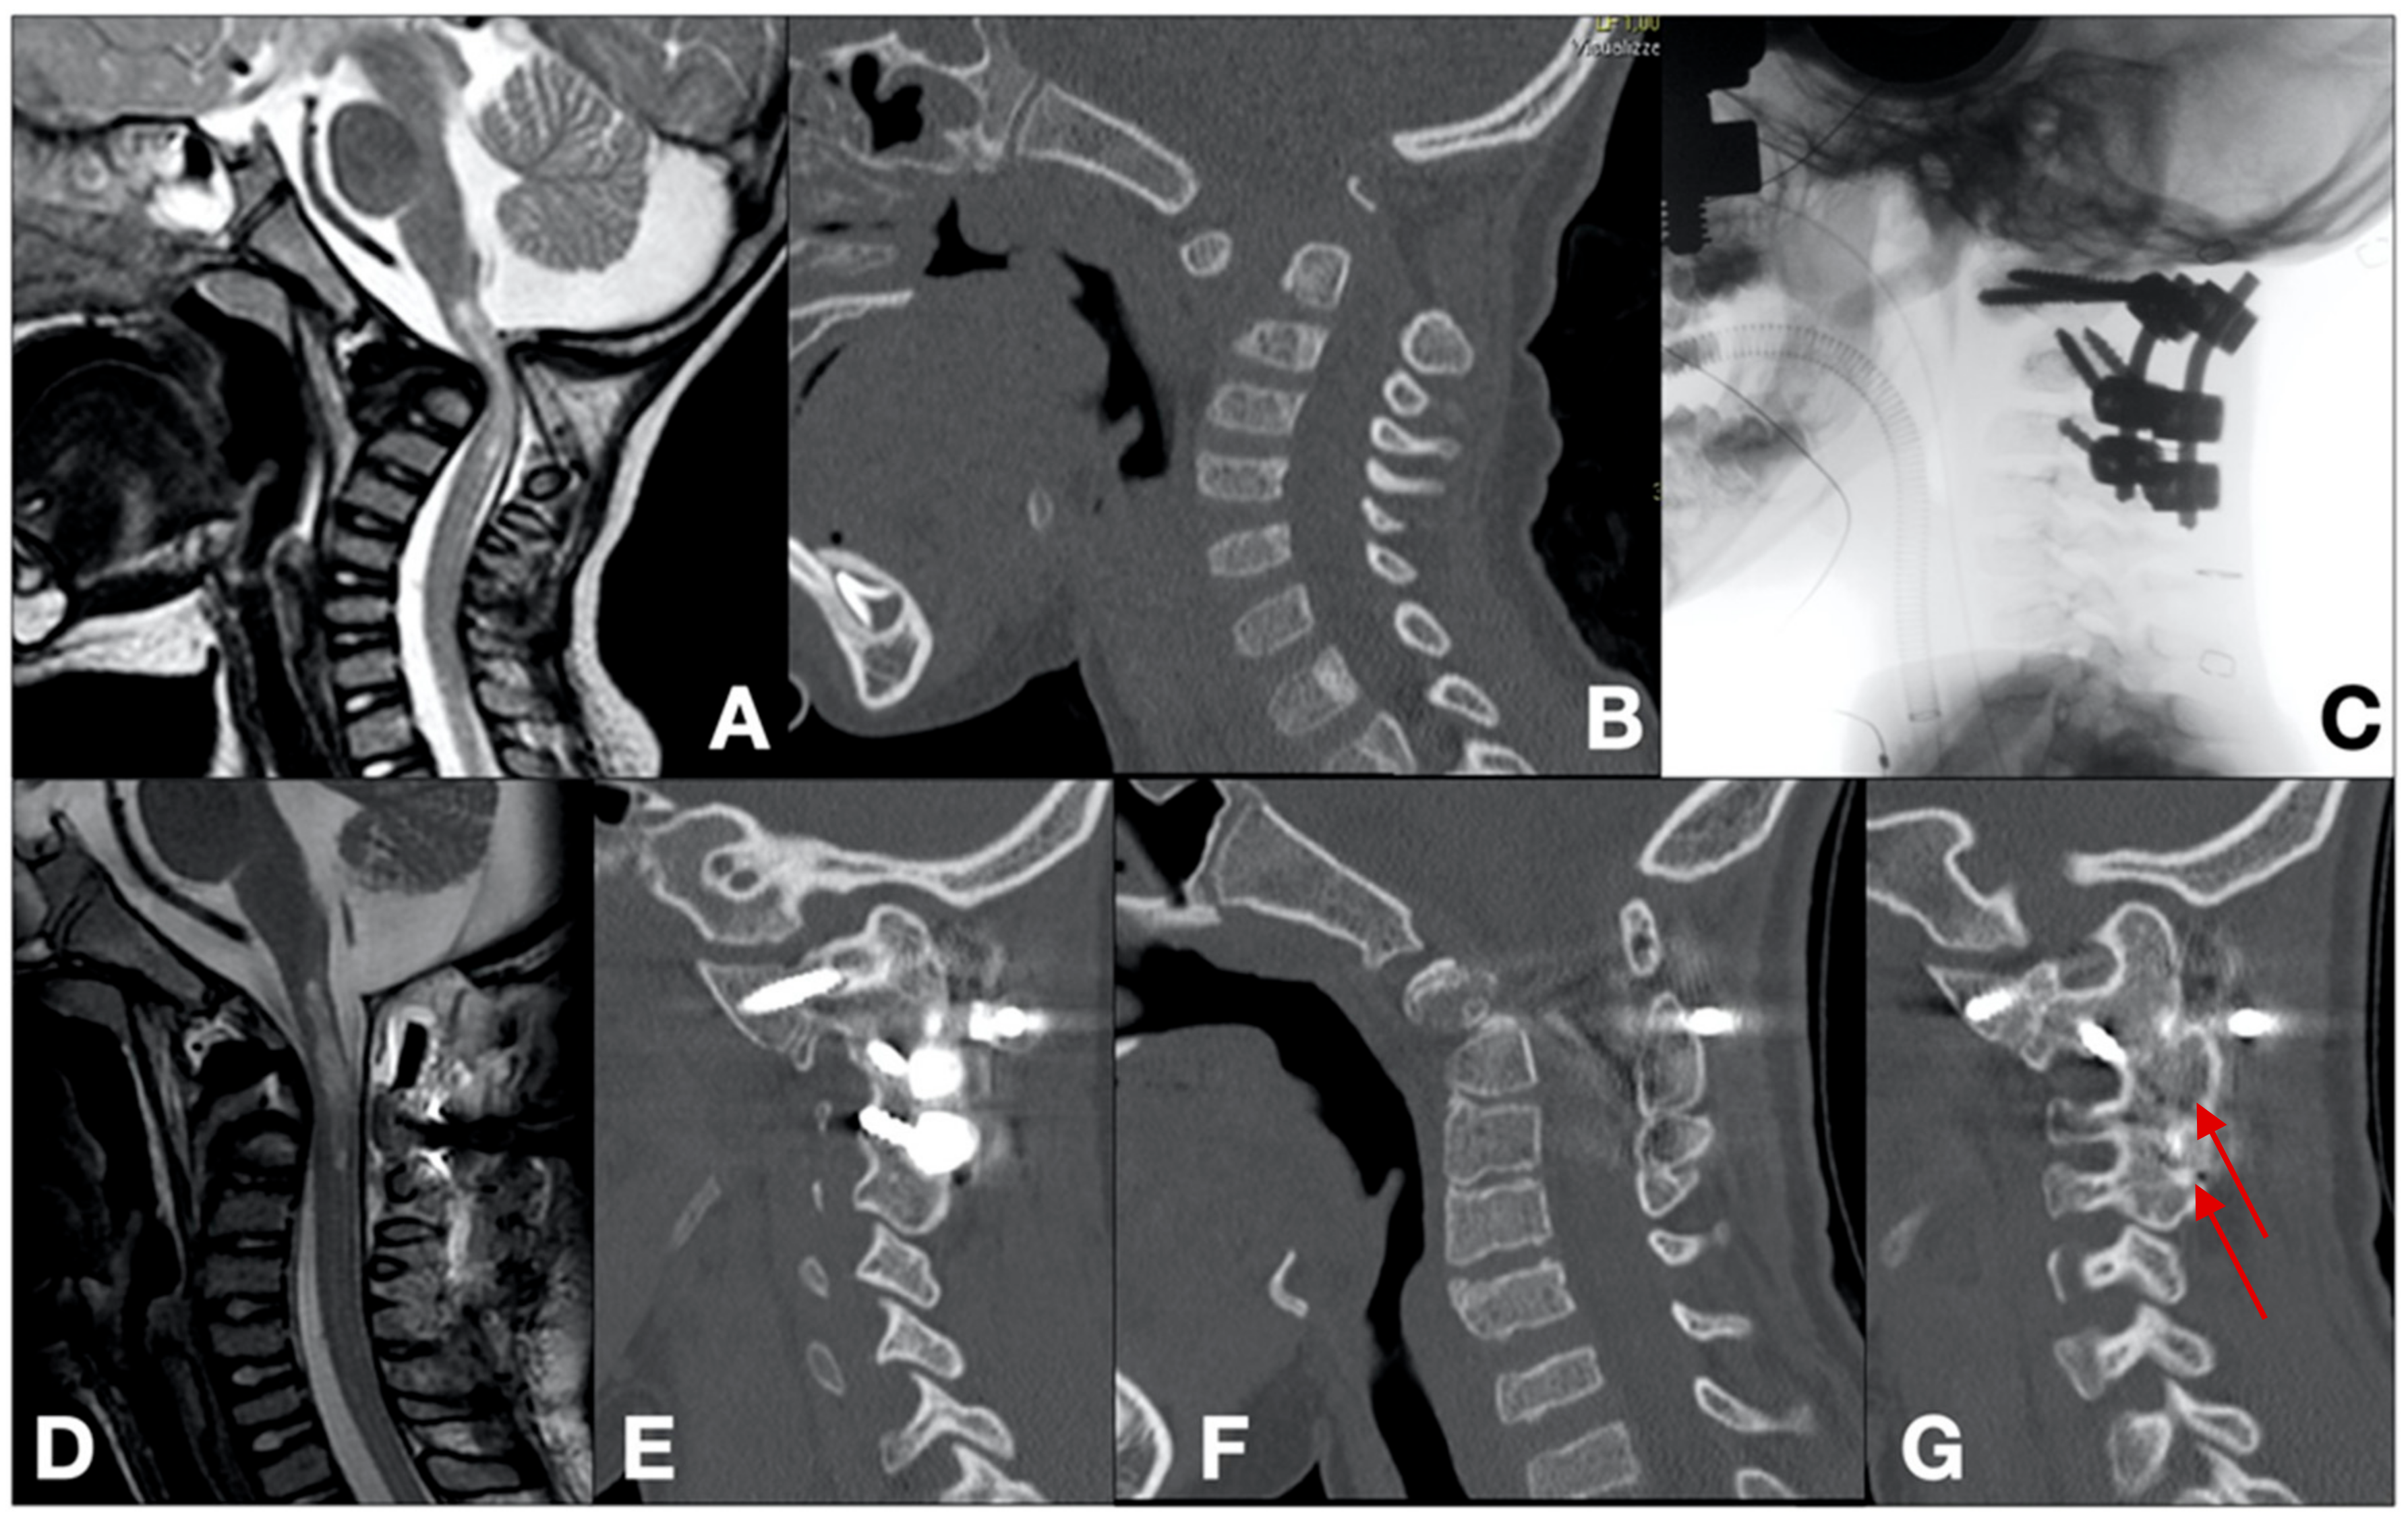

- Case 1 (Figure 1)